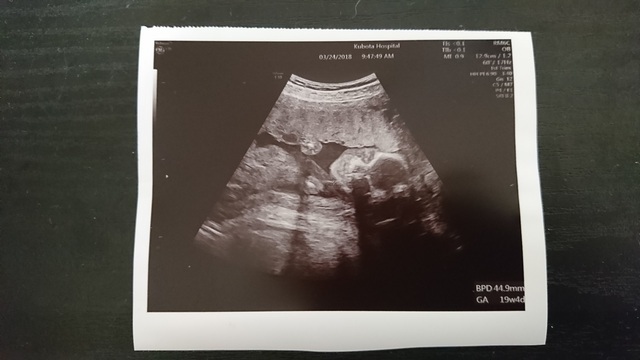

19週3日(19w3d・男の子)|em6 さん(25歳)

エコー写真撮影時のエピソード:

これをとったのが妊娠16週の時でした。性別がわかってパパは嬉しそうだったなぁ〜。お互いの親も嬉しそうで、みんなワクワクです。私もマイカーもまた母子家庭でお互い初孫。嬉しそうでよかったです。はじめのエコーはほんとちっさかったのに、今は腕も足も伸びてバタバタしてて可愛い!こんなに成長していることに驚きです。そんなにたってない感じがするのに、、、。この、エコーの写真を撮るとき違う方向いてたのに、このエコーはこっち見てる!(笑)目が透き通っててホラーみたいでパパと一緒に笑いました。(笑)